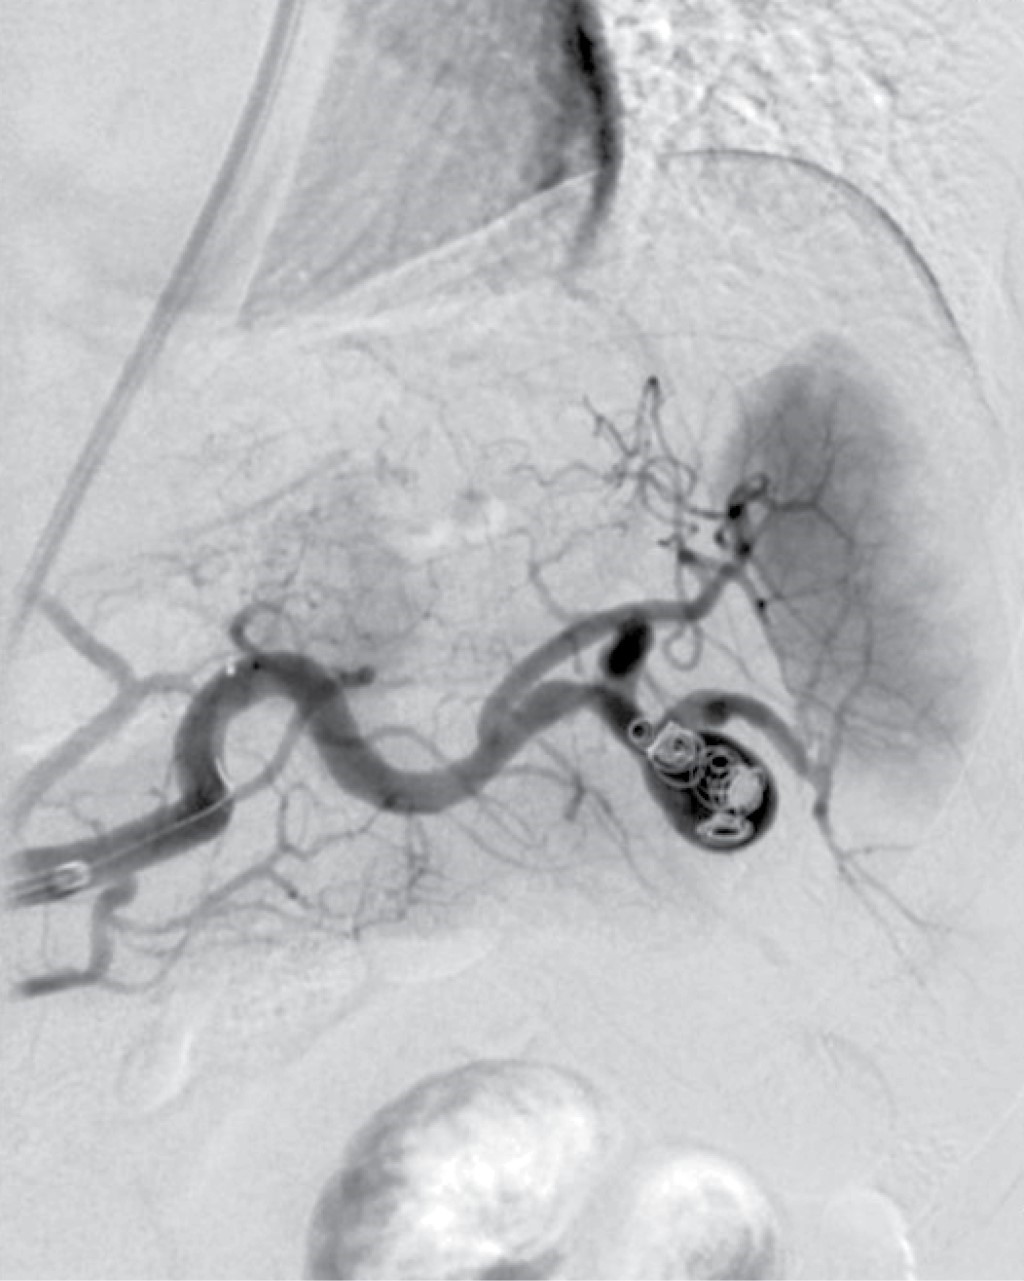

Femenino de 41 años, con antecedente de hipotiroidismo diagnosticado a los 21 años, actualmente sin tratamiento médico desde los 40 años por aparente control, diagnóstico de miomatosis uterina a los 40 años, sin tratamiento; antecedente de dos cesáreas, última a los 23 años, sin complicaciones. Accidente automovilístico con volcadura a los 40 años, sin daño orgánico aparente. Inicia padecimiento actual posterior a accidente automovilístico ocurrido un año previo con dolor en hipocondrio izquierdo, de tipo intermitente, punzante, sin irradiaciones, sin agravantes ni atenuantes; a la exploración física presenta dolor en hipocondrio izquierdo a la palpación profunda, resto sin datos patológicos. Se realizó ultrasonido con hallazgos compatibles con aneurisma de la arteria esplénica y colelitiasis, se complementa abordaje diagnóstico con angiotomografía de aorta abdominal encontrando arteria esplénica de calibre normal, con dilatación focal sacular en segmento distal compatible con aneurisma de 17.7 × 15.9 mm y cuello de 5.5 mm, con trombo mural de 2 mm, sin signos de ruptura, litiasis vesicular y miomatosis uterina. En manejo conjunto con angiología se realiza embolización selectiva con colocación de coils, sin complicaciones aparentes (Figura 1). En el seguimiento inmediato, la paciente presenta dolor abdominal y leucocitosis, se realiza nueva angiotomografía con datos sugestivos de oclusión de arteria esplénica e infarto esplénico (Figura 2). Por los hallazgos comentados se decide realizar esplenectomía y colecistectomía convencional mediante abordaje quirúrgico con incisión en línea media, supraumbilical, con los siguientes hallazgos: vesícula biliar de paredes delgadas, múltiples litos en su interior de 5-10 mm aproximadamente, arteria cística de 2 mm, conducto cístico de 3 mm, bazo de 13 × 10 cm aproximadamente, con múltiples zonas isquémicas, aneurisma de la arteria esplénica a nivel de hilio esplénico, posterior a su bifurcación (Figura 3). Cursa el postoperatorio sin complicaciones, por lo que fue egresada tres días después de la cirugía, recibió vacunación correspondiente para pacientes esplenectomizados. Reporte histopatológico con hallazgos de aneurisma de arteria esplénica con ateroesclerosis, parénquima esplénico con vasos congestivos y colecistitis crónica litiásica.

Figura 3